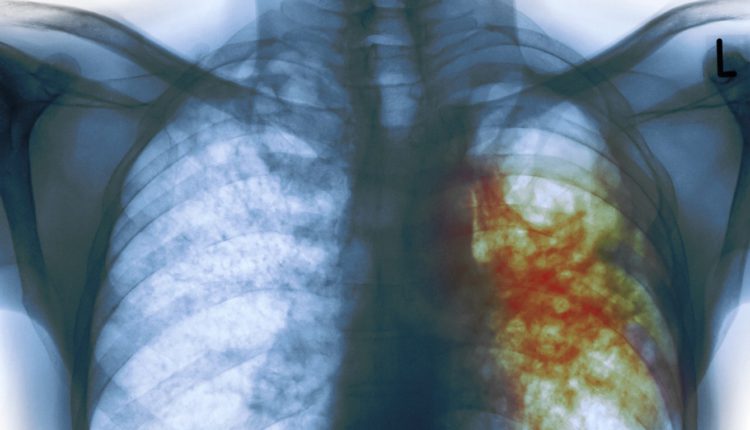

أفادت ذكريات قمارة كاهية مدير بوزارة الصحة ومنسقة البرنامج الوطني لمكافحة السل ، أن تونس تسجّل سنويا 29 حالة عدوى جديدة بمرض السل على كل 100 الف ساكن ، 60 بالمائة منها حالات سل خارج الرئة وخاصة حالة السل اللمفاوي أو العقدي في الرقبة .

وأضافت قمارة، اليوم الأحد، في تصريح لوكالة تونس افريقيا للأنباء، خلال تظاهرة تحسيسية بمدينة العلوم بمناسبة الاحتفال باليوم العالمي لمكافحة السل، أن 78 بالمائة من حالات الإصابة بمرض السل خارج الرئة متأتية من عدوى السل البقري التي يتسبب فيها استهلاك الحليب غير المعقم ومشتقاته ولحوم البقر المصابة ، مشيرة إلى أن وجود استقرار في نسبة الإصابة بالسل الرئوي خلال السنوات الأخيرة، في مقابل تخوف من انتشار مايسمى بالسل اللمفاوي أو العقدي الذي يصيب الرقبة .

وذكرت بأن وزارة الصحة وضعت استراتيجية خماسية لمكافحة السل وأهم قواعدها الكشف المبكر لقطع سلسلة المرض وتحقيق الشفاء التام، معتبرة أن من بين نقاط القوة في مكافحة مرض السل أن الوزارة “تتكفل بالمصابين به من الكشف حتى الشفاء”، وأن الاستراتيجية الوطنية تتضمن محورا كاملا بالشراكة مع المجلس الأعلى للبياطرة ووزارة الفلاحة للعمل معا لمكافحة السل البقري.